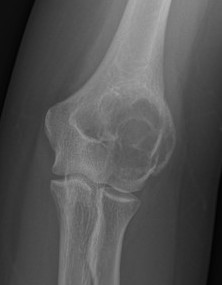

3.  Condyles

- medial: incision through vastus medialis

- lateral: anterior to vastus lateralis

Bony Lesion Lateral Distal FemurFem condyle biopsyFem condyle biopsy